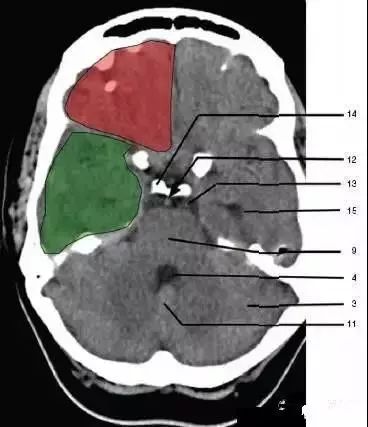

3、小脑(cerebellum)绿色部分为颞叶(Temporal Lobe),浅红色部分为额叶(Frontal Lobe)

9、脑桥(Pons)

11、小脑蚓部(Cerebellar vermis)

12、基底动脉(Basilar artery)

13、桥前池(Prepontine cistern)

14、鞍背(Dorsum sellae)

15、侧脑室颞角(Temporal horn of lateral ventricle):绿色部分为颞叶(Temporal Lobe),浅红色部分为额叶(Frontal Lobe)